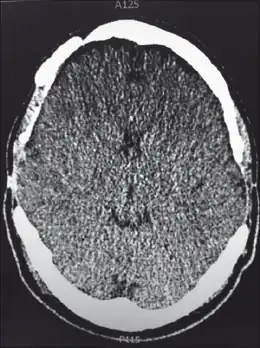

Neuroimaging, usually with computed tomography (CT) or magnetic resonance imaging (MRI), is used to exclude any mass lesions. In IIH these scans typically appear to be normal, although small or slit-like ventricles, dilatation and buckling[13] of the optic nerve sheaths and "empty sella sign" (flattening of the pituitary gland due to increased pressure) and enlargement of Meckel's caves may be seen.